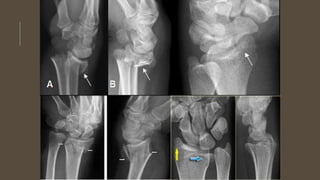

GABINETE

Radiografías:

AP

lateral de muñeca

Lateral con elevación de 15° (esto permite una

adecuada observación de la superficie

articular)

Tac: nos permite la identificación de fragmentos

intrarticulares que en las rx no se observan

RADIOLOGÍA

Esta fractura clínicamente se diagnostica como Fx de Colles y solo el

estudio radiográfico nos da el dx certero.